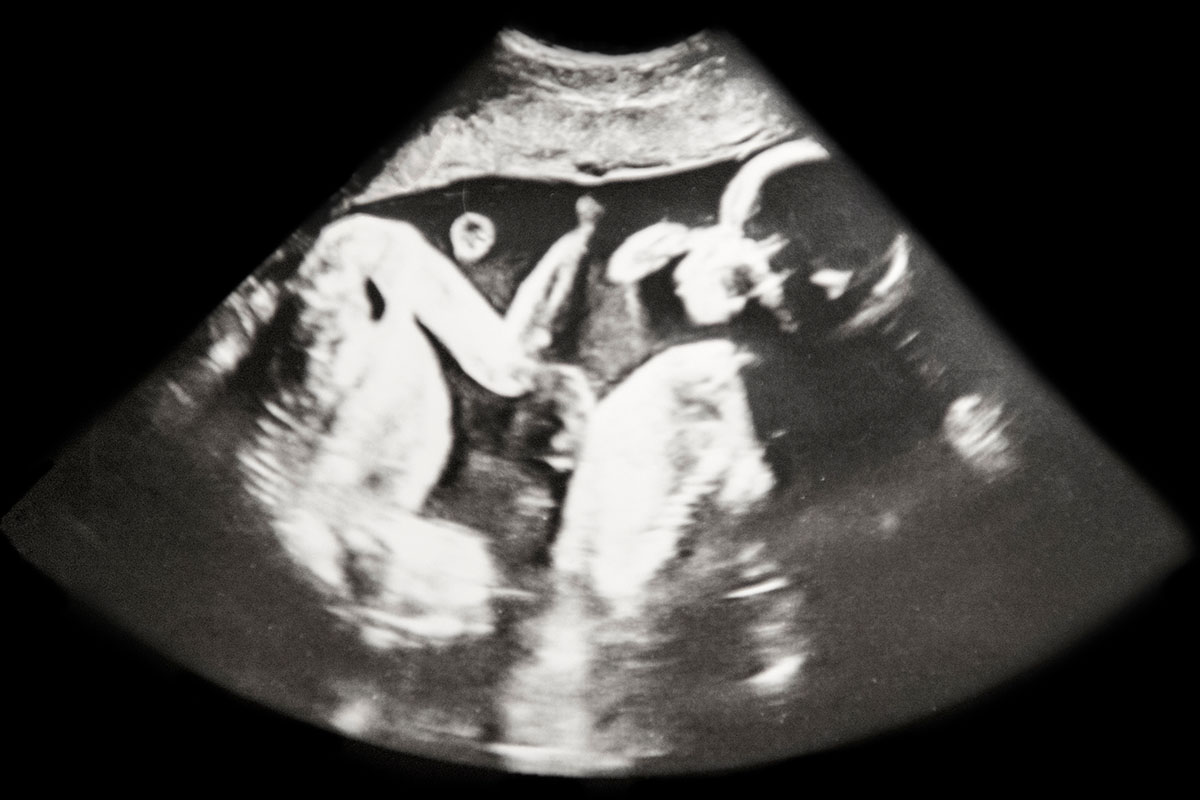

High Risk Pregnancy Center is excited to share one of Dr. Jackson’s latest research studies that takes a thorough look into the assessment and outcomes of twin gestation and its tie to preterm delivery.

Throughout this compelling study, Dr. Jackson worked alongside Hera Women’s Health to identify the tie between cervical length and preterm pregnancy risk as it pertains specifically to twin gestation. Through his thoughtful insight on actionable and measurable ways to bridge the gap between singleton and multiple pregnancies, he could identify the disparities in cervical length as it correlates to an increased risk of preterm birth.

In a recently released abstract, HRPC and Hera Women’s Health shared their insight and results from a years-long research project focused on the tie between transvaginal cervical length and preterm delivery risk in women carrying twins.

As leaders in research related to twin gestation and preterm delivery, and backed by years of proven research, they advocate for performing an early ultrasound of the mother’s cervix every 2 weeks between 16 and 24 weeks to identify patients at risk for preterm delivery.